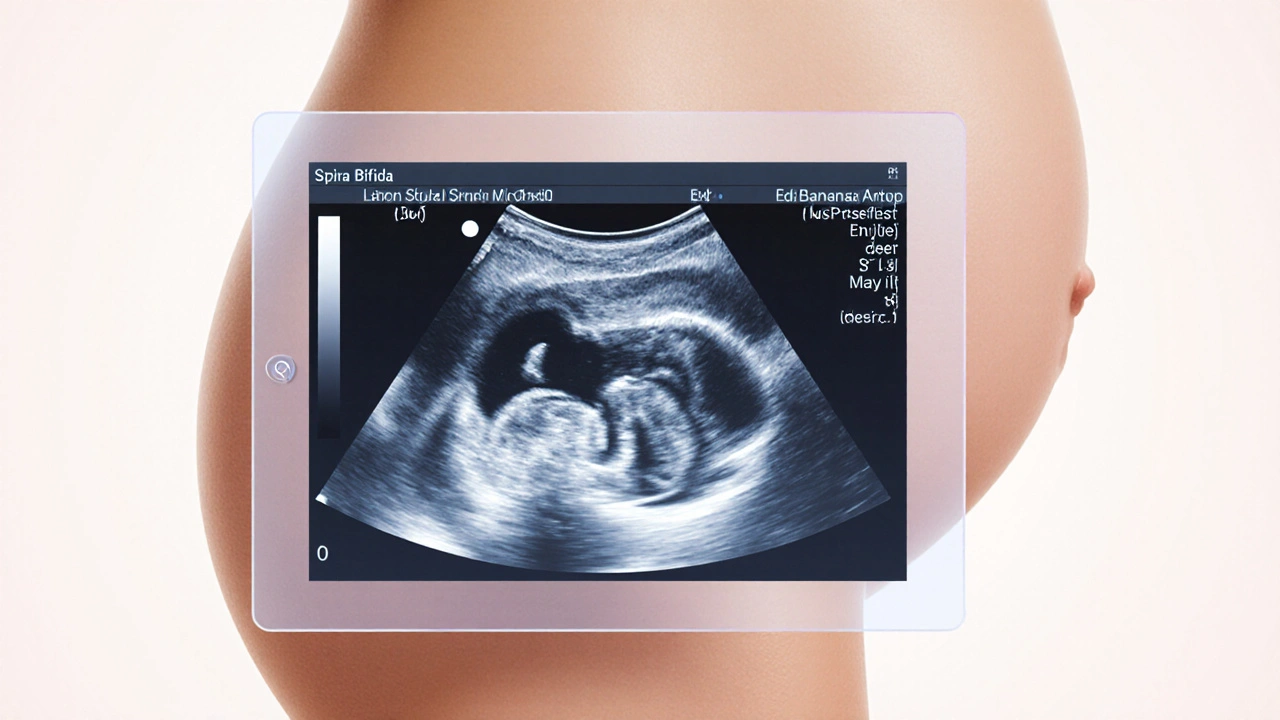

How We Spot Spina Bifida Before Birth

Modern obstetrics offers two main imaging tools:

- Prenatal ultrasound a soundâbased scan performed around 18â20 weeks that can visualize the spine, detect the classic "lemon sign" in the skull, and show the "banana sign" of the cerebellum.

- Fetal MRI a magneticâresonance scan used after 20 weeks to provide detailed images of brain structures and spinal cord involvement.

Ultrasound is the frontline tool because itâs widely available and cheap. When the scan suggests spina bifida, a fetal MRI can confirm the diagnosis, map the exact level of the defect, and assess associated brain changes such as ventriculomegaly (enlarged fluid spaces) that signal hydrocephalus risk.